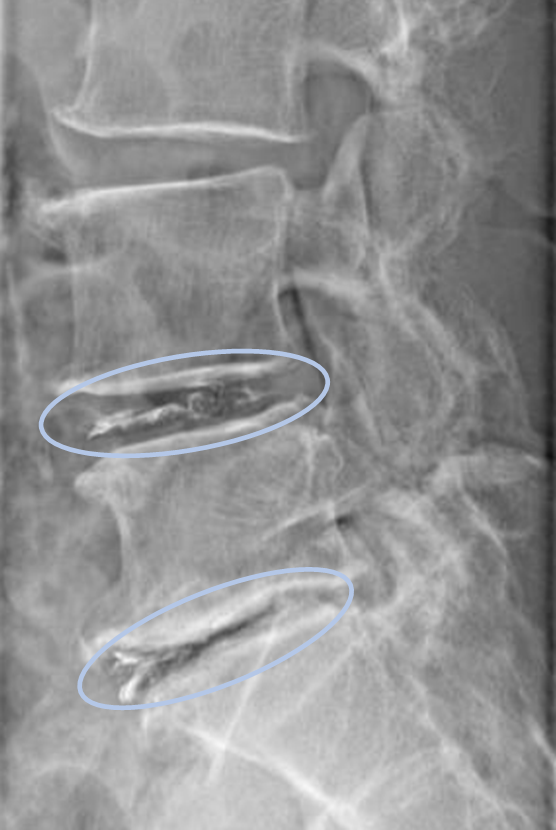

患者様と相談の元、L4/5,5/sにセルゲル法を施行

DiscoGelを入れた後の画像になります。